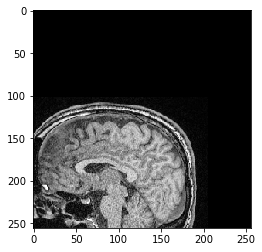

scale_factor = 2

transform = cle.AffineTransform3D()

transform.scale(scale_x=scale_factor)

cle_translated2 = cle.affine_transform(image, transform=transform, auto_size=True)

cle.imshow(cle_translated2[100])